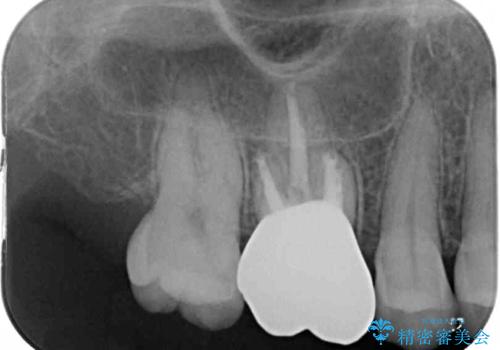

処置後、下顎の膿の出口はすぐに消えましたが、レントゲン写真からも分かるとおり、歯根途中に穴が開いており、充填材が歯根外にはみ出していました。数ヶ月経過を見たところ、特に異常は認められなかったため、補綴治療を行いました。